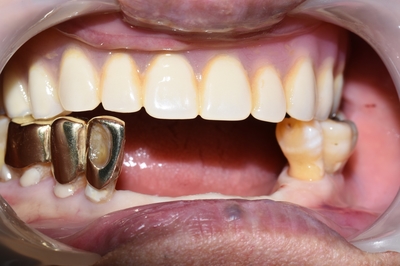

어금니 임플란트를 하고 나시더니 아래 앞니 야매 틀니도 임플란트로 바꾸고 싶어하셨습니다.

그래서 아래 앞니도 임플란트로 하시고 그 중 하나는 보험임플란트를 하셔서

보험임플란트 2개 쓸 수 있는 것을 모두 쓰시고 나머지 몇개는 비보험임플란트까지 흔쾌히 하셨습니다.

아래 앞니도 마찬가지로 네비게이션 임플란트로 시술하였습니다!

연세예감치과에서 아래 쪽 앞니 네비게이션 임플란트 완성 후 사진 ▼

![[종로/시청역]실제 환자의 보험 임플란트, 보험 틀니 사례 소개합니다. 젊어지는틀니,임플란트 치료 관련 이미지 9](https://pub-9f2bb3498faf4d1d8714b41df24753e3.r2.dev/content/clinics/archive/rseeanjxfu/naver_blog/yonseiyegam/assets/by_hash/ca50ea4ef946f12336d4f0b6fe0e5d35e5fd5c2188c6fddd067bba394cf08784.jpg)

요렇게 자연스럽게 완성 되셨구요!!

얼굴도 매우 좋아지셨습니다.